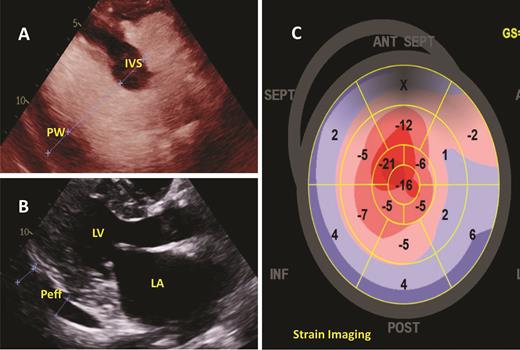

The patient was under the care of a cardiologist since 2017 when she reported lower extremity edema and dyspnea on exertion. More recently, these symptoms had progressed. Bilateral pleural effusions and persistent small pericardial effusion with normal left ventricular ejection fraction (LVEF) were identified by transthoracic echocardiogram (TTE) in February 2019. No unifying diagnosis could explain these findings. A second cardiologist evaluated her when she was in the ED, but still no unifying cardiac diagnosis was confirmed. In September 2019, the patient had progressive dyspnea and underwent a left heart catherization that showed angiographically normal epicardial coronary arteries with an elevated left ventricular end-diastolic pressure (LVEDP) of 20 mmHg, confirming heart failure with preserved ejection fraction. Her heart failure symptoms continued to worsen, requiring hospitalization for further management. A third cardiologist recommended evaluation for cardiac amyloidosis. Repeat TTE confirmed a normal LVEF, mild to moderate concentric hypertrophy, left atrial enlargement, and pericardial effusion in addition to apical sparing in strain imaging (Figure 2). Given the concern for cardiac amyloidosis, an endomyocardial biopsy was performed, confirming amyloid deposits and immunofluorescence that demonstrated the presence of λ light-chain deposition. Mass spectrometry completed in December 2019 confirmed the diagnosis as amyloid light-chain (AL) amyloidosis. Additional laboratory data can be found in Tables 1 and 2.

Two-dimensional transthoracic echocardiogram demonstrating the following: (A) Measuring the interventricular septal (IVS) and posterior wall (PW) thickness, both of which were determined to meet criteria for left ventricular hypertrophy; (B) Parasternal long axis view demonstrating the left ventricle (LV), left atrium (LA), and a small to moderate, posterior pericardial effusion (Peff); (C) strain imaging showing apical sparing, which has been associated with cardiac amyloidosis.